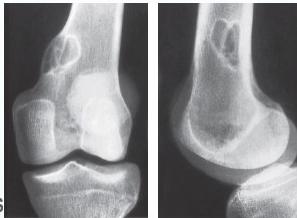

Giant-Cell Tumor

- Unknown origin:

- Giant cells abundant

- Behavior:

- One third benign

- One third locally aggressive

- One third (less) with distant metastasis

- Young adults

- Common sites:

- Around knee

- Proximal humerus

- Distal radius

Radiological Features

- Eccentric lesion:

- Radiolucent

- Soap bubble

- Abuts (adjacent) against the joint

- Thin cortex

- Margins may be clear / unclear:

- Depends on aggressiveness

- Treatment:

- Curettage & bone grafting

- More wide excision in recurrent and aggressive lesions

Source: Bone Tumors A Practical Guide to Imaging